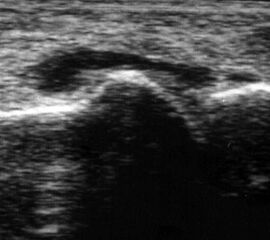

Fibulaverletzung beim Kind

Abgehobenes Periost mit periostalem Hämatom (rechts) mit Gegenseite (links). Die Kortikalis wird unterbrochen von der noch offenen Wachstumsfuge der Fibula.

Abbildung 12

Lagerung: Rückenlage, leichte Innrotation des Fußes.

Schnittebene: LS über distaler Fibula.

Referenzstruktur: Fibula im Längsverlauf.

Befunde: Bei Kindern wird nach Distorsion des OSG mitunter eine Lösung der Fibulafuge vermutet, die jedoch in der klinischen Praxis sehr selten ist. Die seitenvergleichende Untersuchung zeigt dann ein aufgrund des dicken und bei Kindern gut abgrenzbaren echogenen Periosts ein periostales Hämatom, was aber auch ein Hinweis auf eine Fissur oder Fraktur sein kann (Abb.12).